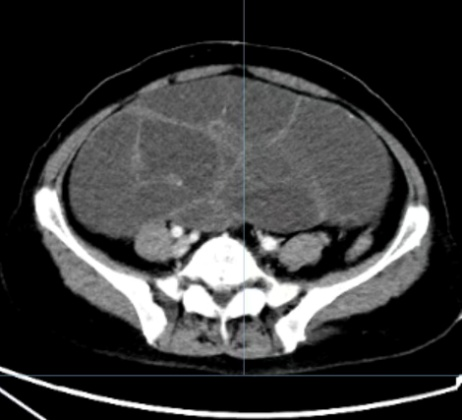

• 胃肠外科成功完成一例巨大血友病腹腔假肿瘤切除术

近日,山一大一附院(省千佛山医院)胃肠外科朱健康教授团队成功为一名长期受血友病困扰、合并罕见巨大腹腔假肿瘤的患者实施手术治疗。该患者曾辗转国内多家医院求医,均因病情复杂、手术风险极高未能开展治疗,最终慕名来到山一大一附院,在多学科...